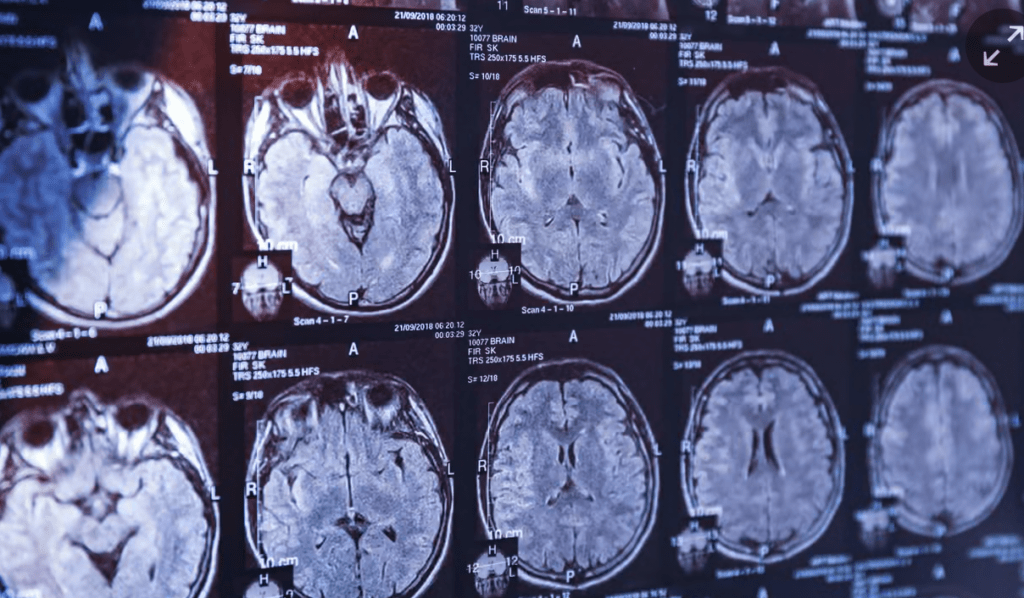

Parkinson’la ilgili en önemli sorun, hastalığın beyindeki dejenerasyon ilerledikten sonra teşhis edilmesi. Genellikle teşhis konduğunda geç de kalınmış oluyor bu yüzden.